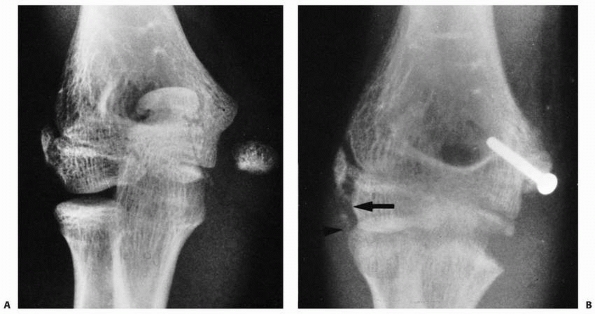

high-quality postoperative MR images to evaluate healing.

FIGURE 15-27 A,B. Fracture of the capitellum in a 14-year-old boy. C,D. After open reduction and fixation with two small cannulated screws through a lateral approach.

|

if an anatomic reduction can be achieved with a minimum of open

manipulation or dissection, then we prefer to reattach it with two

small cannulated screws inserted from posterior to anterior through a

lateral approach. Enough bone must be present in the capitellar

fragment to engage the screw threads, and if possible, countersink the

heads of the screws (see Fig. 15-27). If the